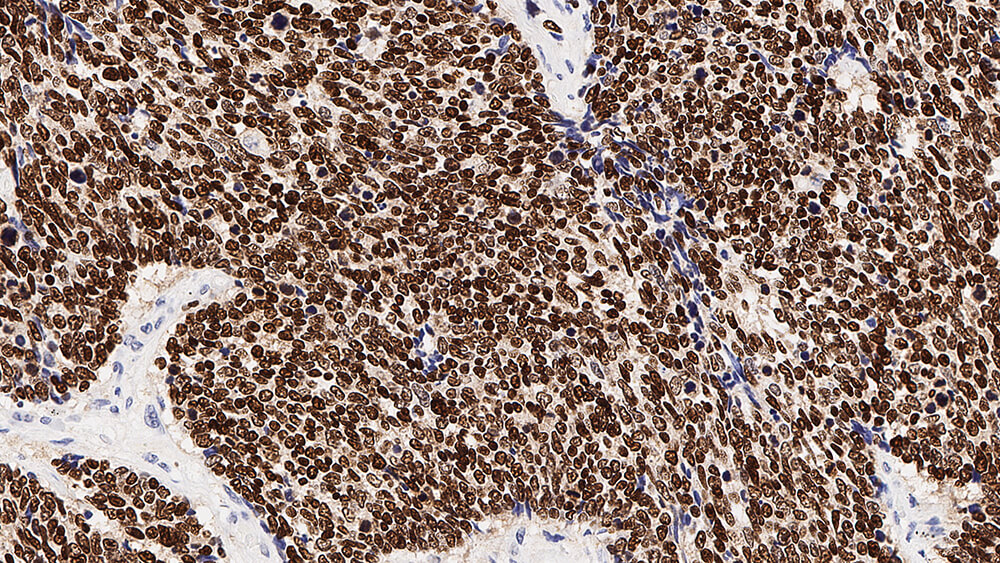

Human thyroid: immunohistochemical staining for Thyroid Transcription Factor-1. Note nuclear staining of thyroid epithelial cells. Thyroid Transcription Factor-1: clone SPT24

O Fator de transcrição da tireoide 1 (TTF-1) é um membro da família do fator de transcrição de homeodomínio e desempenha um papel na regulação de genes expressados dentro da tireoide, pulmão e cérebro. Estes incluem a tireoglobulina, peroxidase da tireoide, proteína de secreção da célula Clara e proteínas surfactantes.

O TTF-1 foi relatado ser expresso em mais de 90% dos carcinomas pulmonares de células pequenas e em 75% dos carcinomas pulmonares de células não pequenas, mas não é expressado em carcinoides pulmonares típicos.

Relata-se também TTF-1 expressado em carcinomas papilares, foliculares e bócio, uma tumefação não maligna da tireoide, mas não em carcinomas de tireoide anaplásticos.